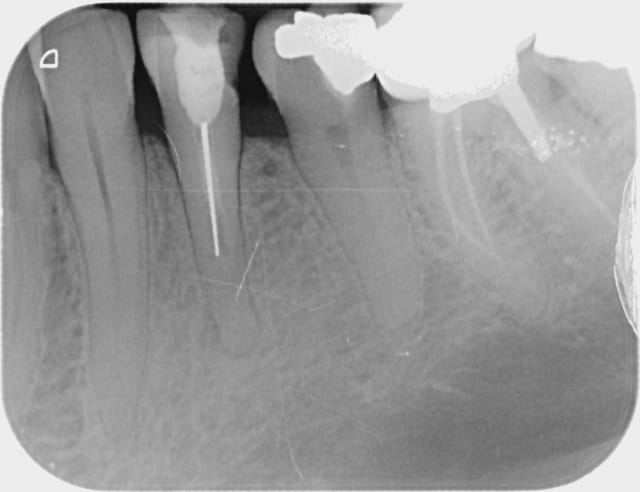

12/03/2012 à 19h55

L'endo papoue :

Alapex jean pierre 000 tblr9u - Eugenol

Il a obturé avec la seringue de l'intra-pulpaire ? Je ne vois pas d'autre explication :p